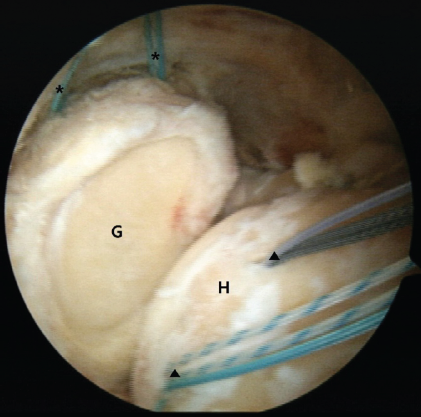

Figure 1: Intraoperative arthroscopy image of posterosuperior irreparable rotator cuff tears of the right shoulder. Due to extensive rotator cuff tears involving the supraspinatus and infraspinatus, there was substantial tendon retraction and shortening to the level of the glenoid, making reattachment to the humeral head footprint unfeasible even after thorough soft tissue release. Two 4.5-mm polyether ether ketone (PEEK) Corkscrew (asterisk) anchors were inserted into the superior glenoid, and two additional 4.5-mm PEEK (arrowhead) Corkscrew anchors were placed into the supraspinatus footprint. G: glenoid; H: humeral head.

In detailed surgical techniques, the lateral decubitus position and general anesthesia were used to prepare the patients. During the diagnostic examination with arthroscopy, the feasibility of repairing the supraspinatus and infraspinatus was assessed. The condition of the subscapularis and the long head of the biceps tendon was first assessed. Subsequently, SCR was carried out following the technique described by Mihata et al. A fascia lata autograft, including the intermuscular septum attached to the gluteus maximus, was harvested to ensure adequate thickness. The graft was folded 3–4 times to achieve a minimum thickness of 6 mm. The superior glenoid rim and the greater tuberosity footprint were decorticated to prepare for graft fixation. Two 4.5-mm PEEK Corkscrew anchors were inserted into the superior glenoid, and another two were placed at the supraspinatus footprint. The medial side of the graft was fixed using a mattress suture configuration, whereas the lateral aspect was secured with a double-row suture bridge technique, performed with the arm positioned in 30° of abduction (Fig. 1). The medial edge of the graft was secured using a mattress suture technique, while the lateral edge was affixed using the double-row suture bridge technique with lateral anchors in the shoulder at a 30° abduction position. After that, the LT tendon was harvested for aLTT. A skin incision approximately 5 cm in length was made along the scapular spine, extending from its medial border. The boundary between the LT tendon and the middle trapezius (MT) tendon was identified, and the LT tendon was separated from the MT tendon. A small incision was made in the infraspinatus fascia to provide a pathway for transferring the LT tendon. Then, the Achilles tendon allograft was folded 2 or 3 times to achieve a minimum thickness of 6 mm, a width of 2 cm, and a length of 15 cm, serving as an interpositional graft. One medial row anchor was inserted into the infraspinatus footprint. The interpositional graft was passed through the infraspinatus fascia into the subacromial space. After being placed on the infraspinatus footprint, the graft was fixed using medial-row and lateral-row anchors. The interpositional graft was connected to the SCR graft with a side-to-side suturing technique (Fig. 2).